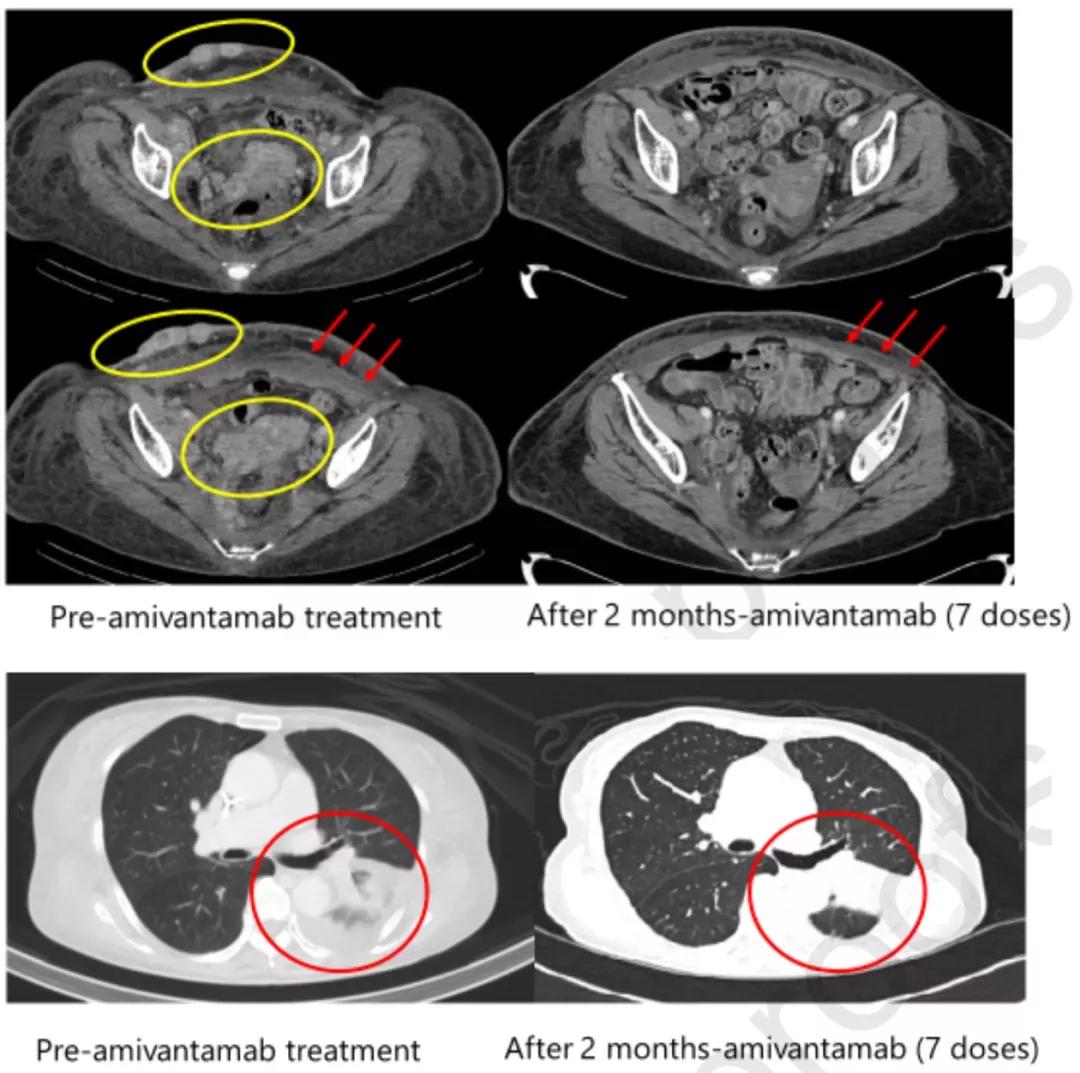

随访时,患者自我感觉好多了。客观的检查随访与女士的症状缓解一致。JNJ-6732治疗后,EGFR扩增数、EGFR三联突变频率及血清CEA水平均明显下降(图2)。与此同时,皮下及腹股沟淋巴结转移几乎消失、胸水明显减少(图3)。在进行这篇报道时,医生再次随访,患者的整体疗效获益已超过了100天。

图3. JNJ-6732治疗前(左)与治疗2月后(右)的影像学资料对比